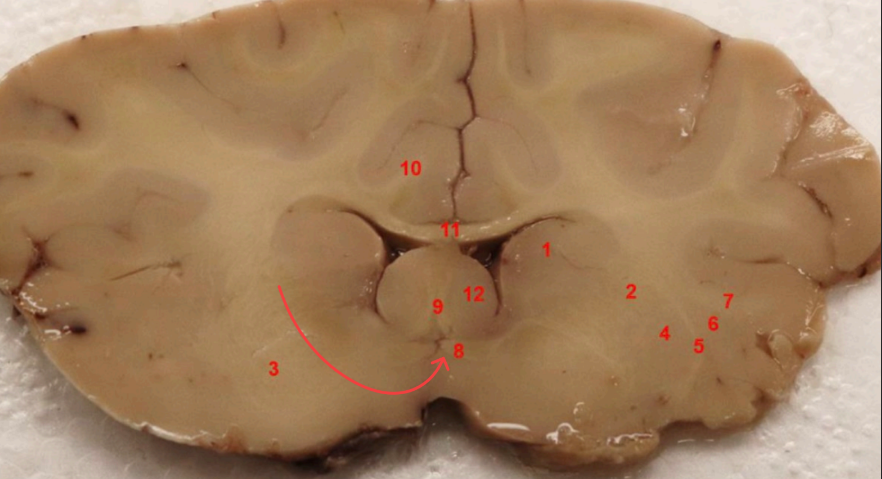

What nuclei is this, function?

Caudate Nucleus , motor control, voluntary movement planning, and procedural learning (habits)

what area is this, function?

nucleus accembus, reward, pleasure, addiction, and motivation.

what tract is this, ?

Cingulum bundle

what COMMISSURE i s this

genu of corpus callosum

what tract is this ? function?

septohypthalmic tract

what ventricle is this

lateral

what area is this

Olfactory Tubercle

what commisure is this

body of corpus callosum

septum pellucidum

what nuclei is this

Caudate nucleus

what capsule is this

external capsule